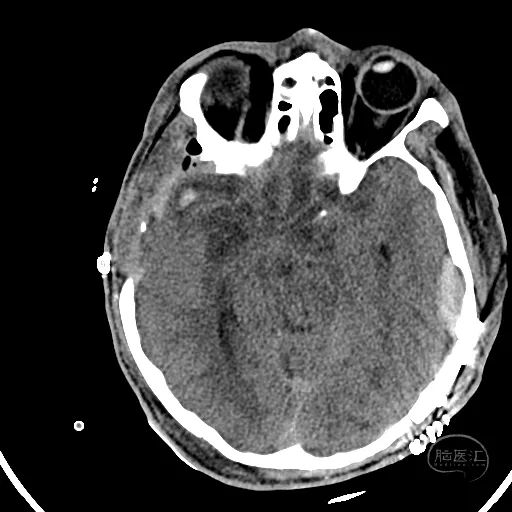

患者,男,53岁,因车祸伤1小时来诊,入院时患者烦躁,GCS评分5分,不能对答,双侧瞳孔等大等圆,直径2mm,对光反射迟钝,四肢躁动,自主呼吸尚稳定。

颅脑CT可见左侧小脑半球挫裂伤,第四脑室明显受压。

右额叶脑挫裂伤并血肿,侧脑室额角受压,脑室无明显扩张。

中线结构稍向左侧偏移。

骨窗显示枕骨粉碎性骨折,累及枕骨大孔左侧,齿突尚居中。